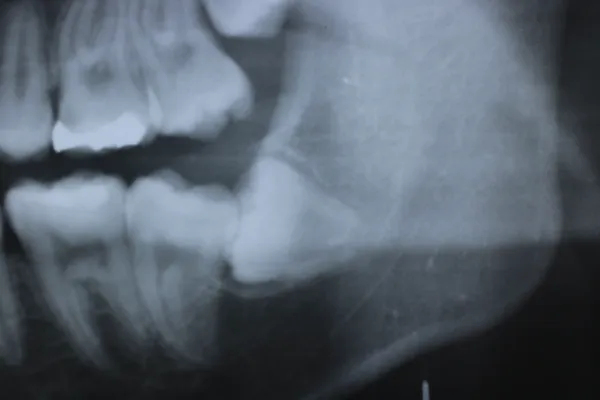

7親知らず

Case7